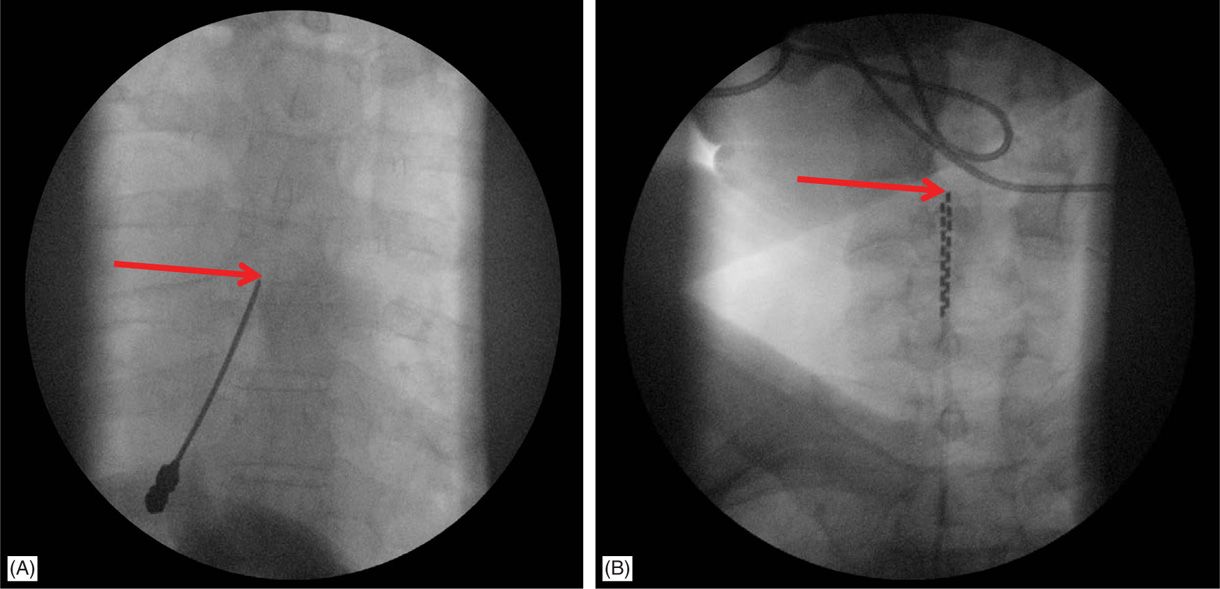

Spinal Cord Stimulation Dr Thomas E Smith

Dual Lead Spinal Cord Stimulator Cpt Cpt® 63650 can be billed either on two separate lines or on one line with a quantity of 2, 3, etc. Please verify with local payers for specific device coding requirements. The information in this article contains billing, coding or other guidelines that complement the local coverage determination. The lead implantation codes 63650 and 63655 may be used for both the trial and permanent implant stages. Cpt® 63650 can be billed either on two separate lines or on one line with a quantity of 2, 3, etc. Coding and payment guide for medicare reimbursement: The following are the 2021 medicare coding and national payment rates for. Insertion or replacement of spinal neurostimulator pulse generator or receiver, requiring pocket creation and connection between electrode. Check national and local policies. Saluda medical offers several resources for coding, coverage, and payment information for spinal cord stimulation. The ama cpt has defined simple intraoperative or subsequent programming of neurostimulator.

From aneskey.com